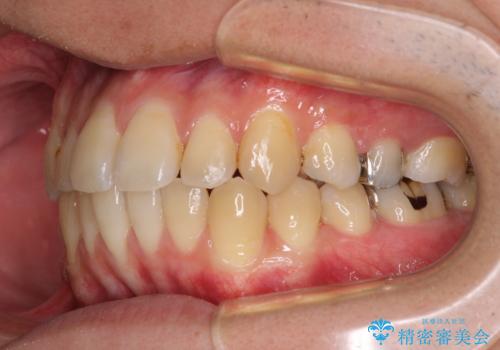

前歯のクロスバイトをインビザラインで矯正治療

- 前歯のデコボコとクロスバイトを気にして来院された患者様です。

前歯を早く整えたいとの希望があったので、ワイヤー矯正にて短期間でクロスバイトを解消し、その後インビザラインにて整えることとしました。

インビザラインによる前歯のクロスバイト改善におけるリスクとして、前歯歯髄充血・歯髄壊死が挙げられます。

ワイヤー矯正を併用する目的として、短期間でデコボコやクロスバイトを改善する他に、歯髄充血リスクを低減させるというものがあります。